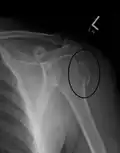

A fracture of the greater tuberosity of the humerus -

Fracture of the greater tuberosity of the humerus -